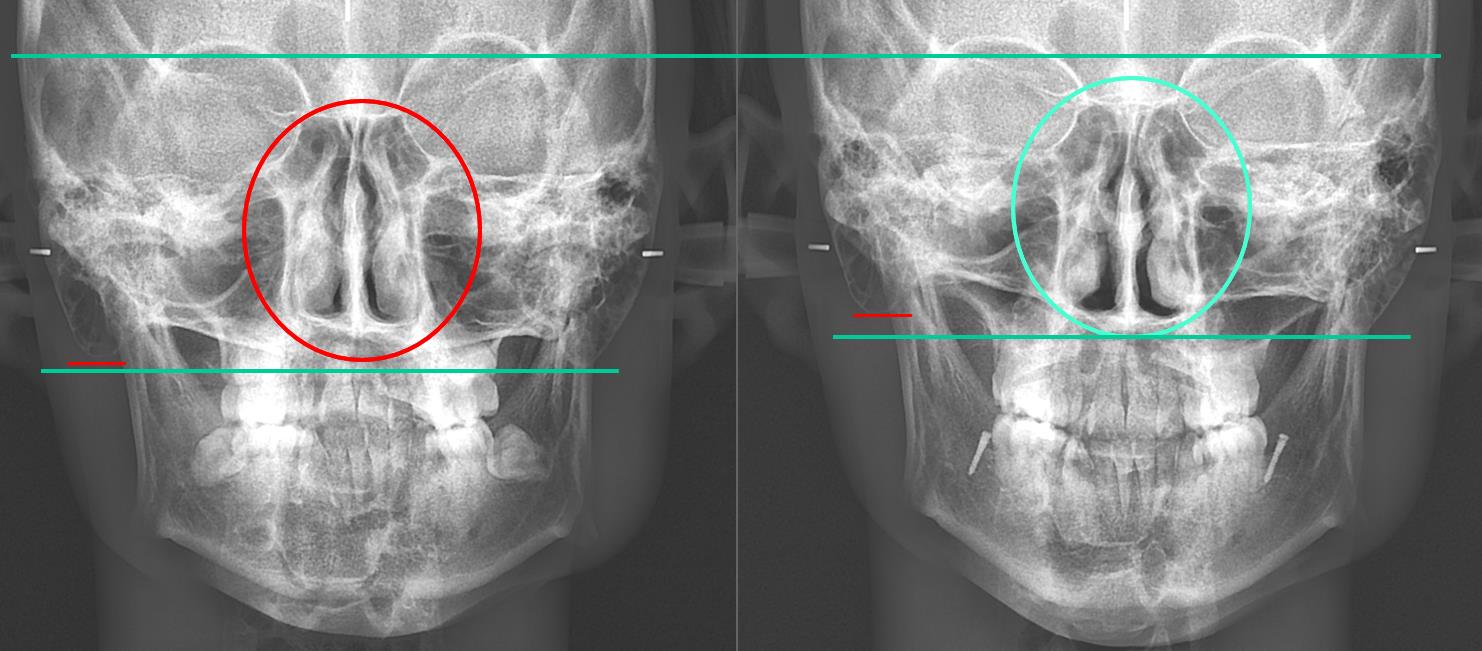

Comparison between MCB-concept Invisalign and conventional Invisalign at other dental clinics .

When the three-dimensional position of the mandible is aligned with the facial midline and the teeth are arranged accordingly, the following changes occur.